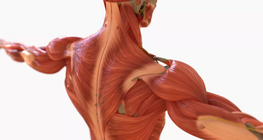

Striated muscle tissue, is one of the three types of muscle tissue present in the human body.

Anatomy of the shoulder and upper extremity.

Anatomy of the upper extremities